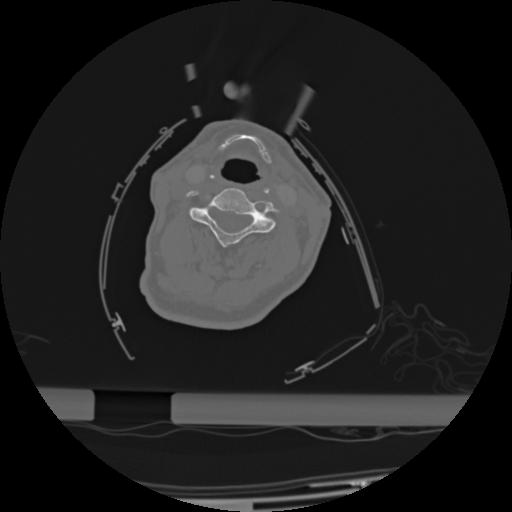

22 ANGIO,CE,Vol,0.5,ANGIO,,